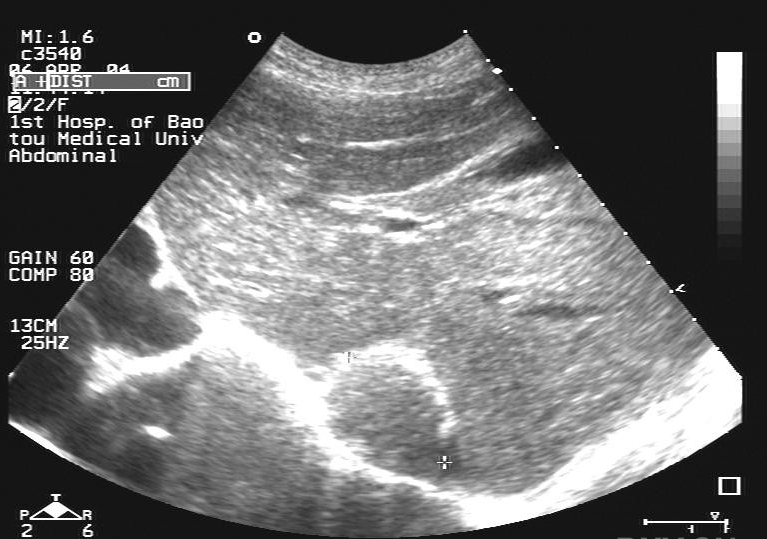

肝内钙化灶是影像学检查中的一种表述,指在B超或CT等检查中发现的肝实质内强光点或高密度影其形成原因多样,最常见的是慢性炎症反复刺激导致的局部钙盐沉积,也可能与血管瘤实性病变或既往感染如肝脓肿寄生虫病后的修复过程有关是否需要治疗需根据具体情况判断1无需治疗的情况多数肝。

一定义肝内钙化灶指肝脏内出现的钙质沉着物,形态类似结石,但并非真正的结石,通常通过B超CT或MRI等影像学检查发现肝内胆管结石则是发生在肝内胆管内的结石,可直接导致胆管阻塞和局部炎症反应二形成原因肝内钙化灶的成因多样,可能与肝内胆管壁钙盐沉积炎症或损伤后疤痕形成寄生虫感染或。

肝内钙化灶是肝脏内钙质沉积形成的强回声灶,通常为稳定病变其形成原因多样,包括肝内胆管结石慢性炎症如血吸虫病寄生虫感染肝脏创伤或肿瘤等多数钙化灶不会直接影响肝功能,但需排除恶性病变可能例如,肝内胆管结石可能合并感染或胆汁淤积肿瘤相关钙化需警惕转移性病灶综合诊断需结合病史。

肝内钙化灶是肝脏局部受炎症感染后,肝细胞缺血坏死留下的疤痕,通常无需特殊治疗,但特殊情况下需就医一肝内钙化灶的定义肝内钙化灶在肝脏超声检查中表现为高回声图像,提示肝脏既往可能存在慢性炎症病毒感染或外伤其形成机制为肝组织受损后,经过修复过程,损伤部位先发展为慢性纤维化,随后逐渐。